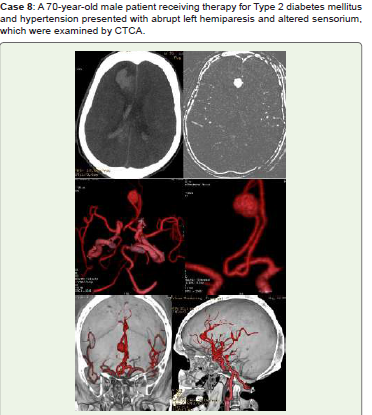

Figure 8:Noncontrast axial (A) show Right frontal lobe lobulated hematoma

with surrounding edema, acute SAH and intraventricular hemorrhage, MIP

(B), 3D-VR (C, D), and virtual dissection of skull images (E, F) all show a

large right precallosal ACA (A3) saccular aneurysm projecting to the right.

He received conservative treatment and advised endovascular coiling and/

or surgical clipping, and frequent follow-up.